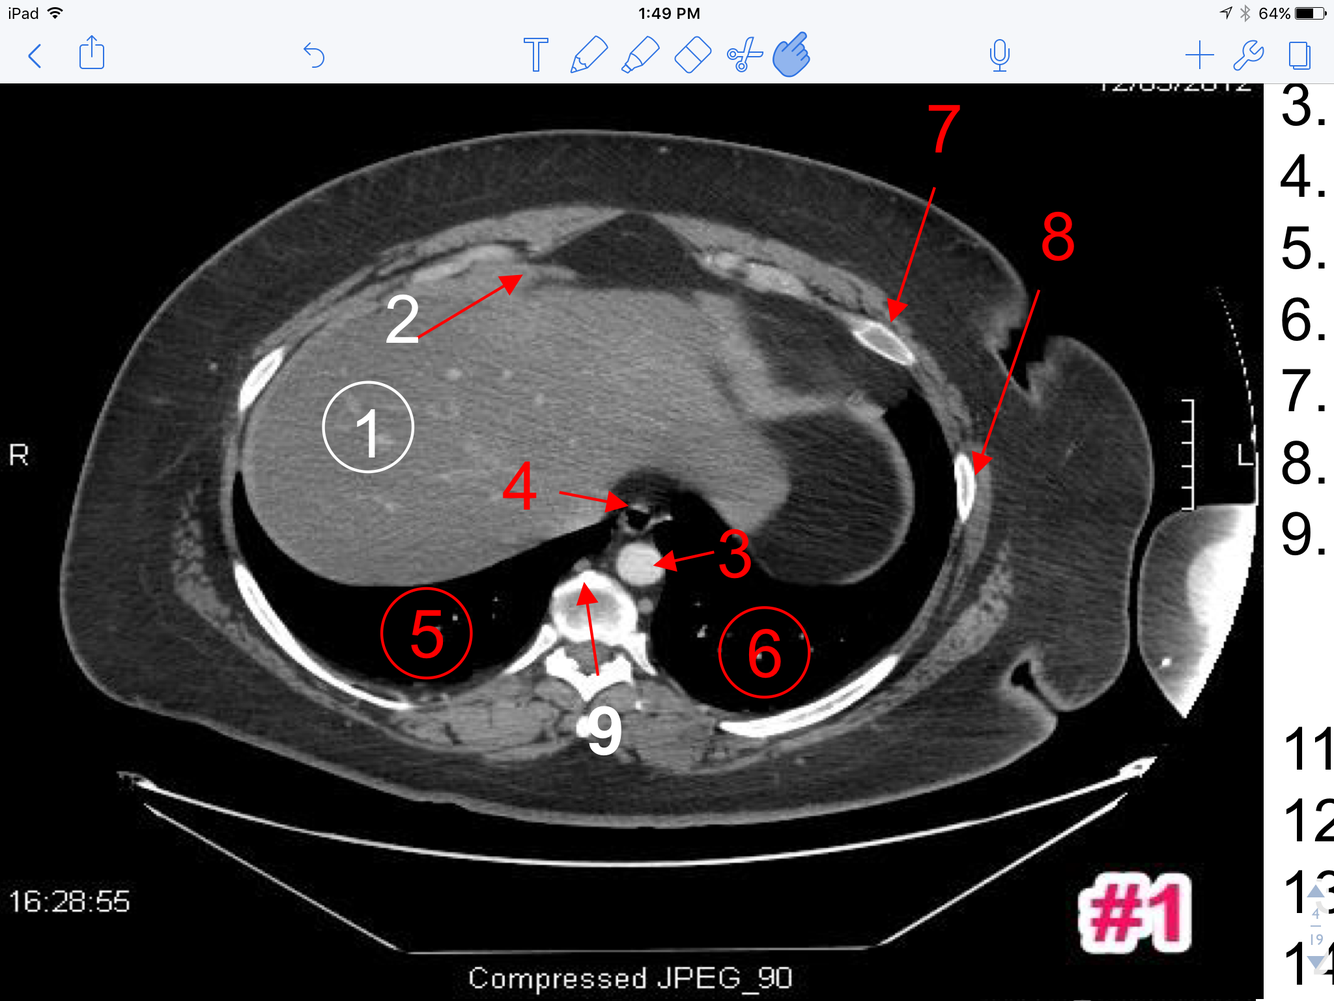

1

A

1. Liver

2. Faliciform ligament

3. Abdominal aorta

4. Abdominal esophagus

5. Rt lung

6. Lt lung

7. Lt lung

8. Lt rib

9. Azygos vein